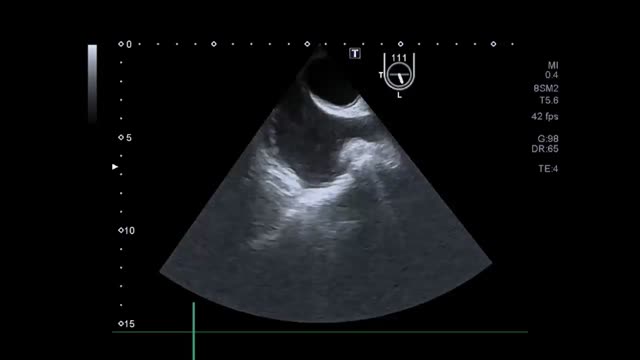

Valoración del volumen sistólico (fig. 2)Se puede realizar por medio de la integral velocidad-tiempo (IVT) y el diámetro del tracto de salida del ventrículo izquierdo (TSVI).

Estimación del volumen sistólico (VS) y del gasto cardiaco (CO) a través de la integral de velocidad (VTI) y radio (r) del tracto de salida del ventrículo izquierdo (TSVI). A) Paraesternal izquierdo ventrículo izquierdo en sístole. B) Zoom TSVI. C) Doppler pulsado TSVI 5C apical. D) Cálculos.

Un IVTTSVI<11cm se correlaciona con un índice cardiaco <2 l/min17,18.